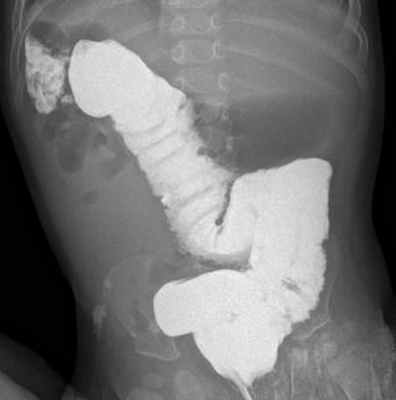

Следующий тип мальротации характеризуется наличием только двух поворотов вместо естественных трех, горизонтальная часть двенадцатиперстной кишки вращается позади оси брыжеечных сосудов, короткий корень брыжейки не прикреплен, вследствие чего могут возникать связки Ледда. На ирригограмме слепая кишка и восходящий отдел толстой кишки расположены высоко, смещены несколько правее от позвоночного столба (рис. 2, 3).

Рис. 2. Ирригограмма в прямой проекции. Отмечается атипичная топография толстой кишки. Слепая кишка расположена высоко в правом фланке брюшной полости, и восходящая часть ободочной кишки расположена вдоль позвоночного столба справа